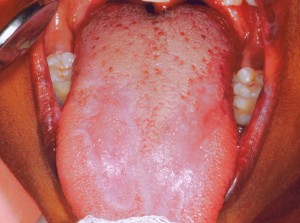

На слизистой оболочке полости рта папулы беловато-перламутрового цвета до 2 мм в диаметре, сливаясь, образуют сетку, причудливый кружевной рисунок либо бляшки серовато-белого цвета. Высыпания локализуются преимущественно на слизистой оболочке щек по средней линии, языка, губ, десен и реже на небе и дне полости рта, а также красной кайме губ. Различают следующие клинические формы: типичную гиперкератотическую, экссудативно-гиперемическую, эрозивно-язвенную.